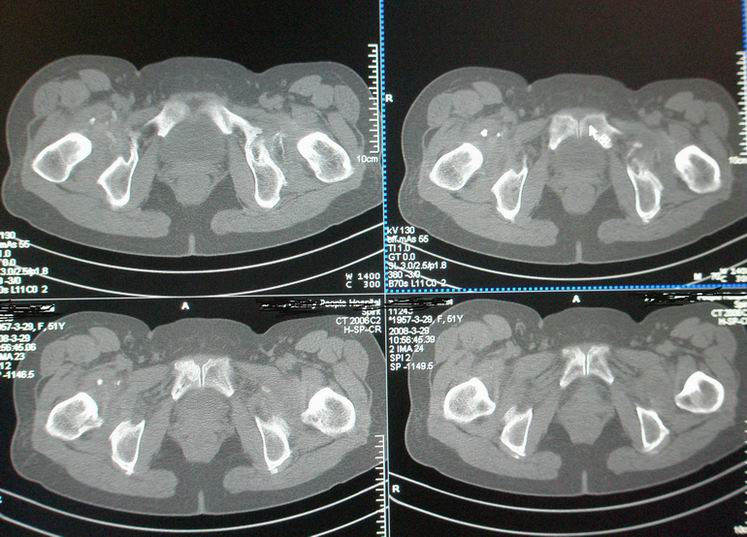

标题: CT12535:女,51岁.双髋痛多年,近加重,左腿难伸直. [打印本页]

标题: CT12535:女,51岁.双髋痛多年,近加重,左腿难伸直.

双髋无菌坏死(重度)??

先天性髋臼发育不良性骨病。双侧股骨头改变为继发性退变。

成人髋臼发育不良性骨关节病.是由于髋臼先天发育不良、髋臼角变大,部分股骨头位于髋臼以外,持重部位少,长期站立、负重造成髋臼退行性骨关节病,主要x线表现是:髋臼变浅平,髋臼角增大,ce角小于30度,髋关节骨性关节面增生硬化,关节间隙变窄,髋臼及股骨头可有囊变.但股骨头变形轻微,与股骨头坏死相比,预后好,可两三年变化不大,而股骨头坏死早期关节间隙不窄或增宽,等到间隙变窄时股骨头已明显变形.

鉴别:股骨头缺血坏死

髋关节创伤性骨关节炎

双侧髋关节退行性骨关节病